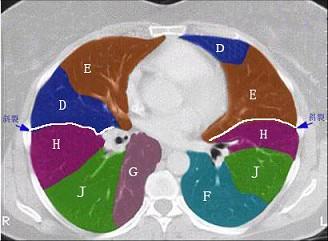

问题 结合肺段模式肺动脉干与右肺动脉层面肺动脉干与右肺动脉层面、心室层面、主动脉弓层面、 左右心房层面(如图),选出左肺上叶的组成 ( )

选项 A.A+B B.A+B+C C.A+B+C+D D.A+B+C+D+E E.A+B+C+D+E+F

答案 D